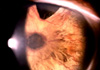

潛伏期1-3d,兩眼同時或相隔1-2d發病。發病3-4d時病情達到高潮,以後逐漸減退。表現為患眼紅、燒灼感,或伴有畏光、流淚。結膜充血,中等量粘膿性分泌物,夜晚水面後,上下瞼睫毛常被分泌物粘合在一起。視力一般不受影響,如分泌物附於角膜表面時,可致一過性視力模糊或虹視。病情較重者可出現結膜下出血。肺炎球菌、流感嗜血桿菌Ⅲ型(Koch-Weeks桿菌)所致結膜炎,可在瞼結膜表面覆蓋一層假膜。流感嗜血桿菌Ⅲ型感染處還可並發卡他性邊緣性角膜侵潤或潰瘍。部分患者伴有體溫升高、身體不適等全身症狀。